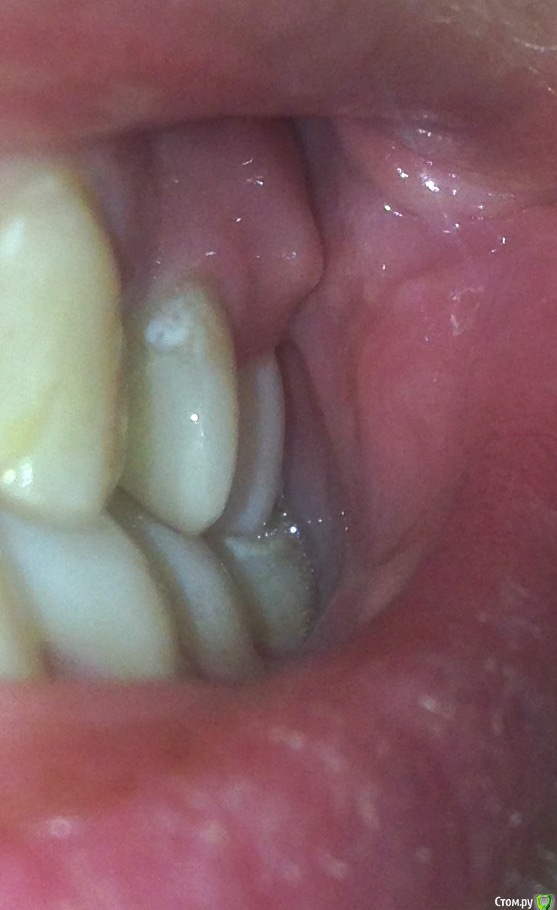

Никто не знает что с этим делать, сказали что пища попадает из за этого подтекает, Ещё 8 на имплант давит и может его расшатать правда такое возможно? Сказали купить ирригатор и постоянно мазать метрогилом. Нерв удалён почти 10 лет назад, пролечен зуб качественно, карман и свищ образовались в этом году.

Вот старый снимок, лучше видно как залечен зуб и свежее фото, сохраняется отёк, болит если надавливать.